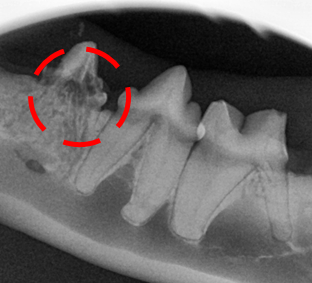

→ 치과 방사선에서도 뚜렷하게

307번의 치아흡수병변이 확인됩니다.

치아흡수병변의 확진은 치과방사선으로 확인합니다.

확인 결과, 방사선상 흡수병변이 발견되었습니다.